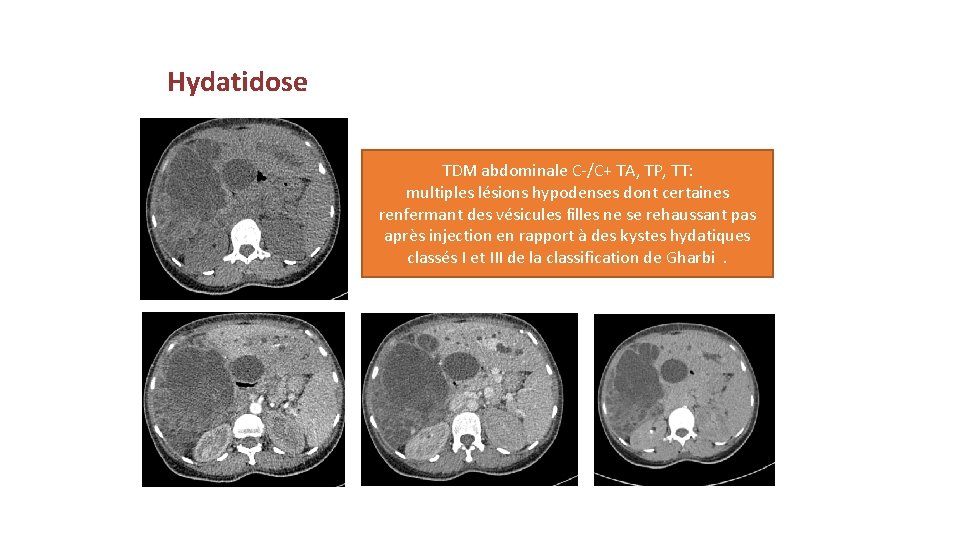

Hydatidose TDM abdominale C-/C+ TA, TP, TT: multiples lésions hypodenses dont certaines renfermant des vésicules filles ne se rehaussant pas après injection en rapport à des kystes hydatiques classés I et III de la classification de Gharbi.

Kyste hydatique Il s’agit d’une pathologie très fréquente, qui survient à tout âge surtout les jeunes spécialement. La transmission se fait de façon accidentelle par l’ingestion des larves EG. Le foie et le poumon sont les localisations les plus fréquentes. • Peut se manifester par un syndrome de masse ou lors d’une complication ictère (par compression des voies biliaires). • Imagerie: retrouve les différents types selon la classification de Gharbi •